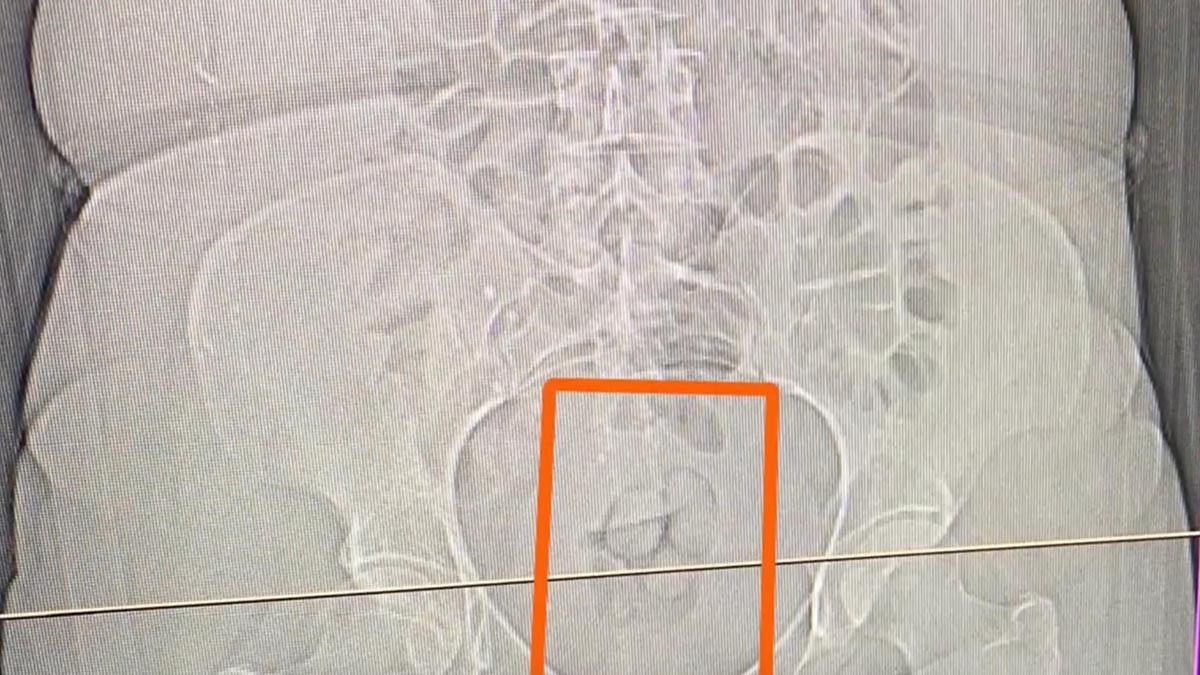

Şüphe üzerine hastaneye götürülen S.S'nin çekilen tomografi görüntülerinde, mide ve bağırsaklarında yabancı cisim olduğu tespit edildi.

21,39 GRAM MİDEDEN ÇIKARILDI

S.S'nin yuttuğu 21,39 gram sentetik uyuşturucu, tıbbi müdahaleyle mide ve bağırsaklarından çıkarıldı.